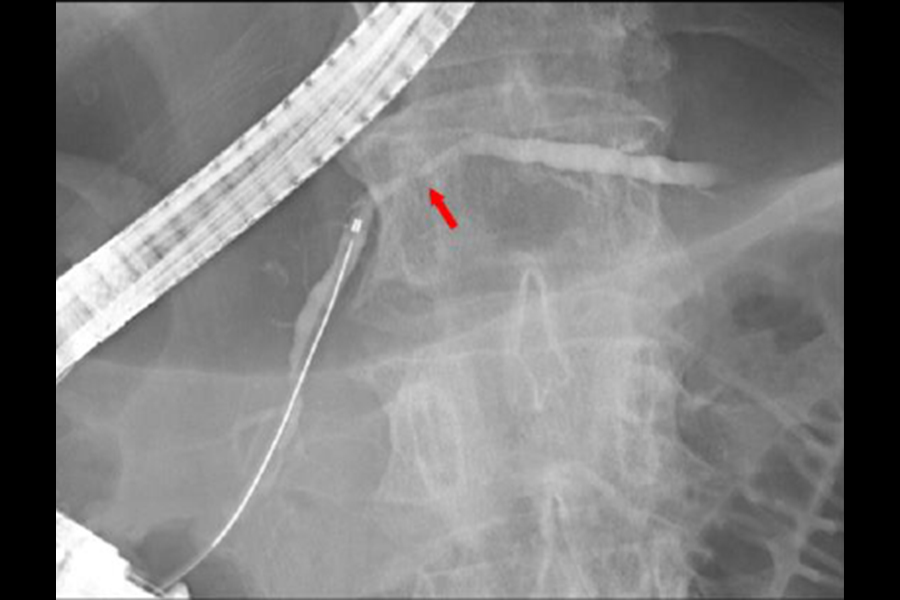

EUS で腫瘤として描出されなくても、膵癌が疑われる所見(主膵管狭窄や限局的な膵実質萎縮など)がある場合は、非常に小さな膵癌の可能性がありますので、ERP(内視鏡を用いた膵管造影検査)を行って膵管内の膵液を採取し、細胞診を行います。最近では、ERPに引き続いて膵管内に細いチューブを 1 日ほど留置し、チューブを介して経鼻的に体外に排出される膵液を繰り返し採取して細胞診に提出する“連続膵液吸引細胞診(SPACE)”という方法を積極的に行っており、早期診断を目指した取り組みを行っています。

写真は、限局性の主膵管狭窄(赤矢印)に対してSPACEを行い、上皮内癌(ステージ0)を診断した症例です。